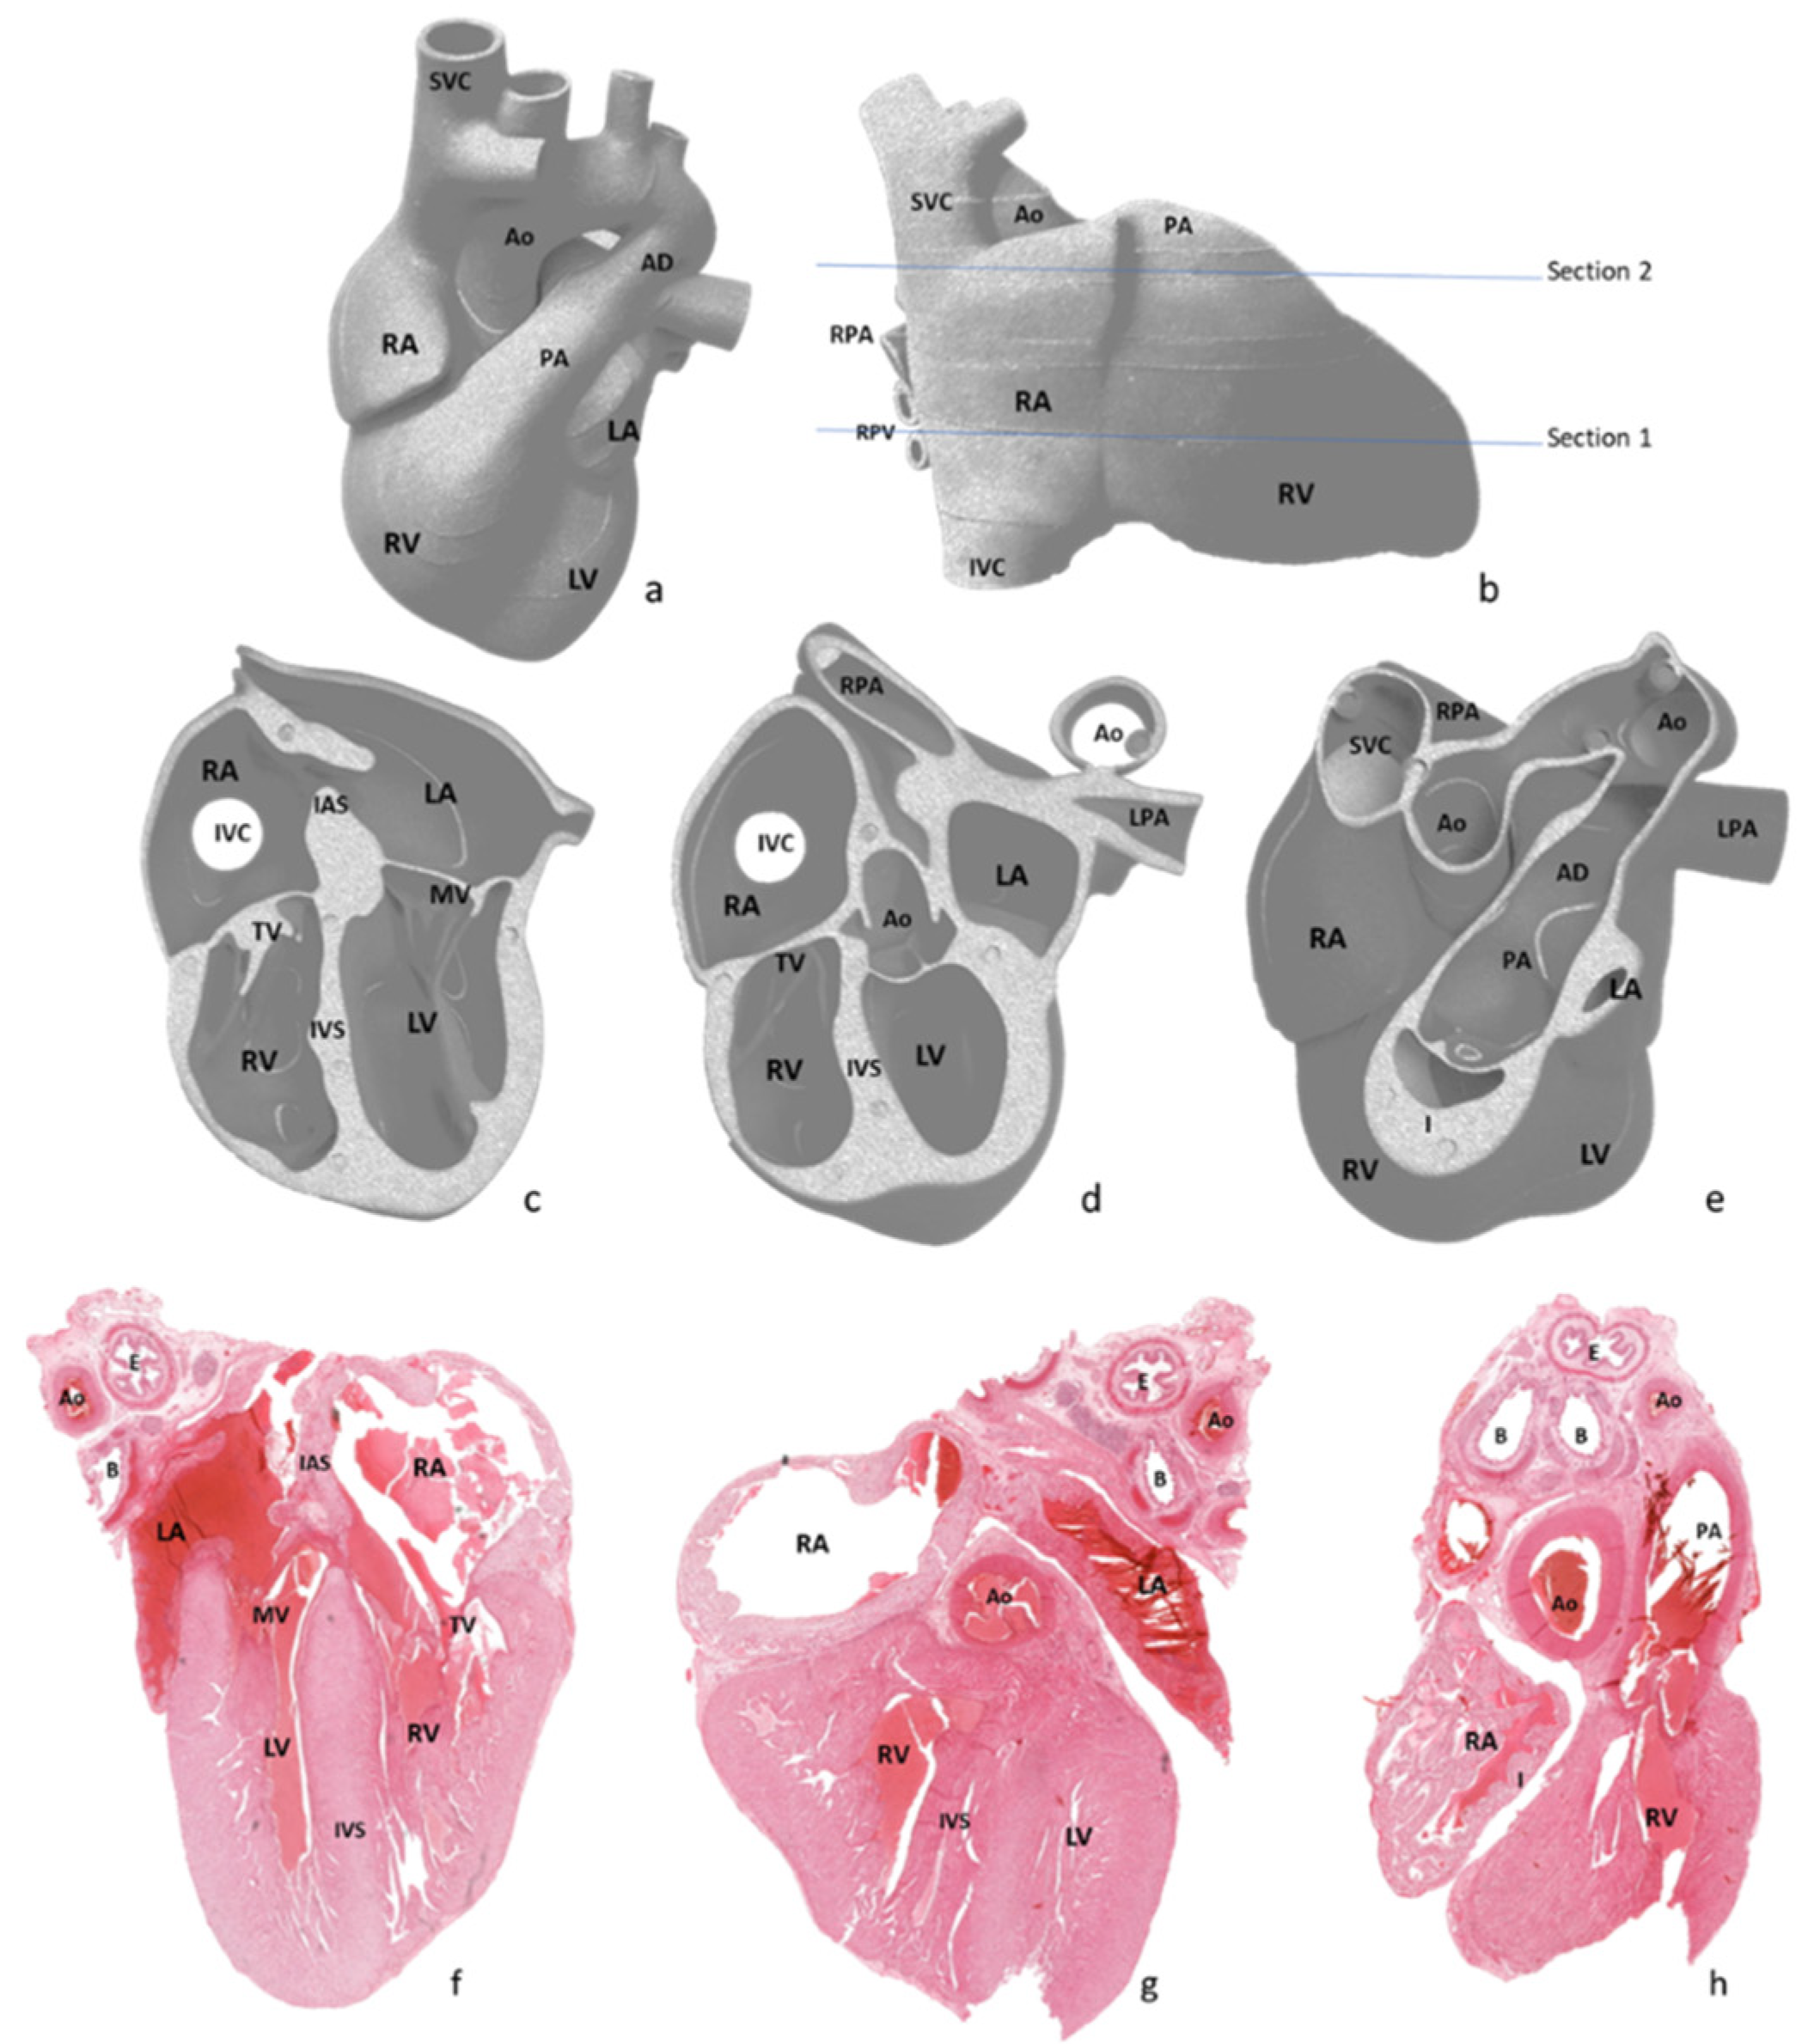

After external examination, two longitudinal sections were performed parallel with the diaphragmatic surface of the heart, as depicted in

Figure 2a,b. The first section was performed through both ventricles and both atria, obtaining a four-chamber view. The second section was performed parallel to the first through the infundibulum and pulmonary artery valve. All obtained sections were processed using a vacuum infiltration processor, namely Tissue-Tek VIP 5 Jr (Sakura, Alphen aan den Rijn, The Netherlands), and embedded in paraffin blocks.

Due to inclusion and sectioning techniques, microscopic sections of the inferior side of the heart were a mirrored view of the macroscopy because the section was flipped over during the paraffin embedding. For the other two sections, the left–right sides corresponded to the external cardiac view, as depicted in

Figure 2c–h and

Figure 3, hence, after sectioning, they were included without flipping.

The pathologic four-chamber examination protocol is described schematically in

Figure 4.